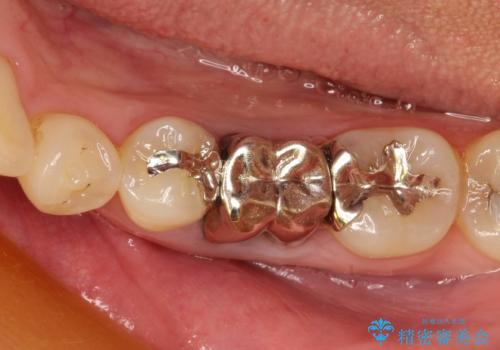

- 保存不可能な歯の抜歯後、待時にてインプラントを埋入、2回法にて咬合回復を計画した。

同時に、前後の歯の金属のやり直しも行った。

インプラントの種類:strauman SLActive

かぶせ物の種類:Bellezza screw retain